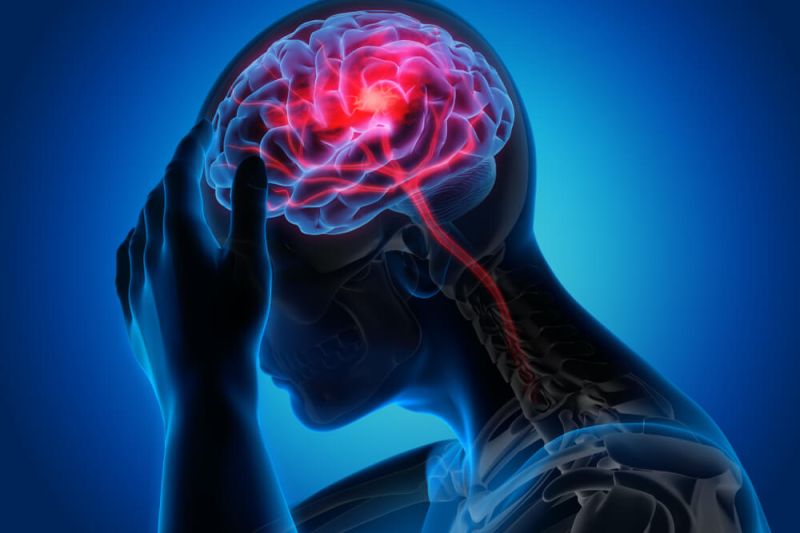

Canabinoides podem limitar crescimento de tumores e atuar diretamente na morte de células cancerígenas, sem danificar os tecidos saudáveis

O câncer de próstata é uma das principais causas de morte entre homens em todo o mundo e atinge principalmente os idosos. Porém, com o avanço dos tratamentos, a chance de cura e sobrevida torna-se maior a cada ano. Uma das técnicas que chamam a atenção da comunidade científica atualmente é a utilização de medicamentos com Cannabis, que podem potencializar a ação da quimioterapia nos pacientes.

“Além dos efeitos paliativos dos canabinoides, pesquisas nas últimas décadas demonstraram seu potencial promissor como agente antitumoral”, aponta a publicação.

“A Cannabis medicinal potencializa a ação da quimioterapia ou do tratamento hormonal que o oncologista determinar para o paciente. Esse tipo de medicamento por si tem um efeito antitumoral, pois diminui a multiplicação das células cancerígenas e aumenta a morte dessas células seletivamente, sem atuar em células sãs”.

“A Cannabis já possui alguns estudos in vitro, in vivo em animais, e, no caso da terapia para câncer de próstata, já existem estudos em humanos com um pequeno número de pacientes, que mostram essa eficácia na apoptose. Apesar desses estudos ainda serem com grupos limitados, devem avançar muito mais agora, já que a Organização das Nações Unidas retirou a Cannabis do rol das drogas altamente viciantes e perigosas, reconhecendo sua função medicamentosa”, afirma.